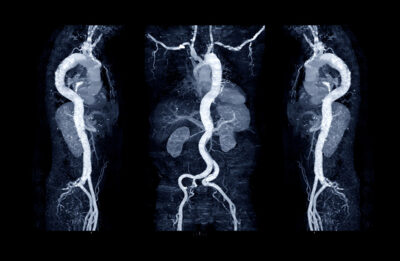

Does Ascending Aorta Size Predict Dissection?

SYNOPSIS: A large Australian database study has shown that, because of the much larger number of patients without severe aortic dilatation, almost all fatal dissections occur in individuals with non-severely dilated aortas — the so-called aortic paradox.

Recent publications have highlighted the fact that many patients who have aortic diameters below the surgical cutoff of 5.5 cm and without genetic aortopathy experience acute thoracic aorta dissection or rupture. Thus, these investigators analyzed the National Echocardiographic Database of Australia (NEDA), which is a highly diverse population of equal sex distribution with > 1 million inpatient and outpatient echocardiograms in 630,000 adults. In 2019, this registry was linked to the National Death Index (NDI) of Australia.

In patients with more than one echocardiogram, the most recent one was used. Patients with prior aortic valve replacement or aortic surgery were excluded. Aorta diameters were taken from the sinuses of Valsalva or the proximal aortic root and categorized as normal (< 4 cm), mild dilatation (4 cm to 4.4 cm), moderate (4.5 cm to 5.5 cm), and severe > 5.5 cm. In subgroups where height or weight was reported, indexed measurements were assessed. Blood pressure was obtained from the echocardiographic report and categorized as hypertension (systolic blood pressure [SBP] > 140 mmHg) or severe hypertension (SBP > 180 mmHg or diastolic BP > 110 mmHg). The primary outcome was death caused by aortic dissection or ruptured aneurysm.

After excluding those with no aorta measurements, the final cohort consisted of 524,994 unique patients with a median age of 64 years of whom 52% were men. Normal aorta diameter was found in 88% of patients, mild dilatation was found in 10% of patients, moderate dilatation was found in 1.9% of patients, and severe dilatation was found in 0.1% of patients. After a median follow-up of seven years, 899 patients died of aortic dissection (median age 77 years, 60% men). The mean time from echocardiogram to dissection was 11 years. Compared to those with normal aortic diameters, death caused by dissection was increased with mild aortic dilatation (odds ratio [OR], 3.05; 95% confidence interval [CI], 2.61-3.56); moderate (OR, 4.0; 95% CI, 3.02-5.30), and severe (OR, 28.72; 95% CI, 18.44-44.72). However, because of the greater number of those without severe dilatation, 98% of fatal dissections occurred in those without severe dilatation. Indexing for height or body surface area did not change the results.

Of the 5,248 patients with bicuspid valves (1%), only five died of dissection. If the 38% of patients with severe dilatation who underwent surgery are considered dead at the time of surgery, the death rate in this group increases from 2% to 24%. The authors concluded that since severely dilated proximal thoracic aortas account for only 2% to 24% of fatal dissections, we need better risk predictors in those without severe dilatation.